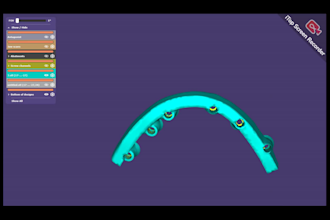

I will do dental prosthesis crown design using exocad, 3shape, inlab and cerec

From $20

Offers video consultations